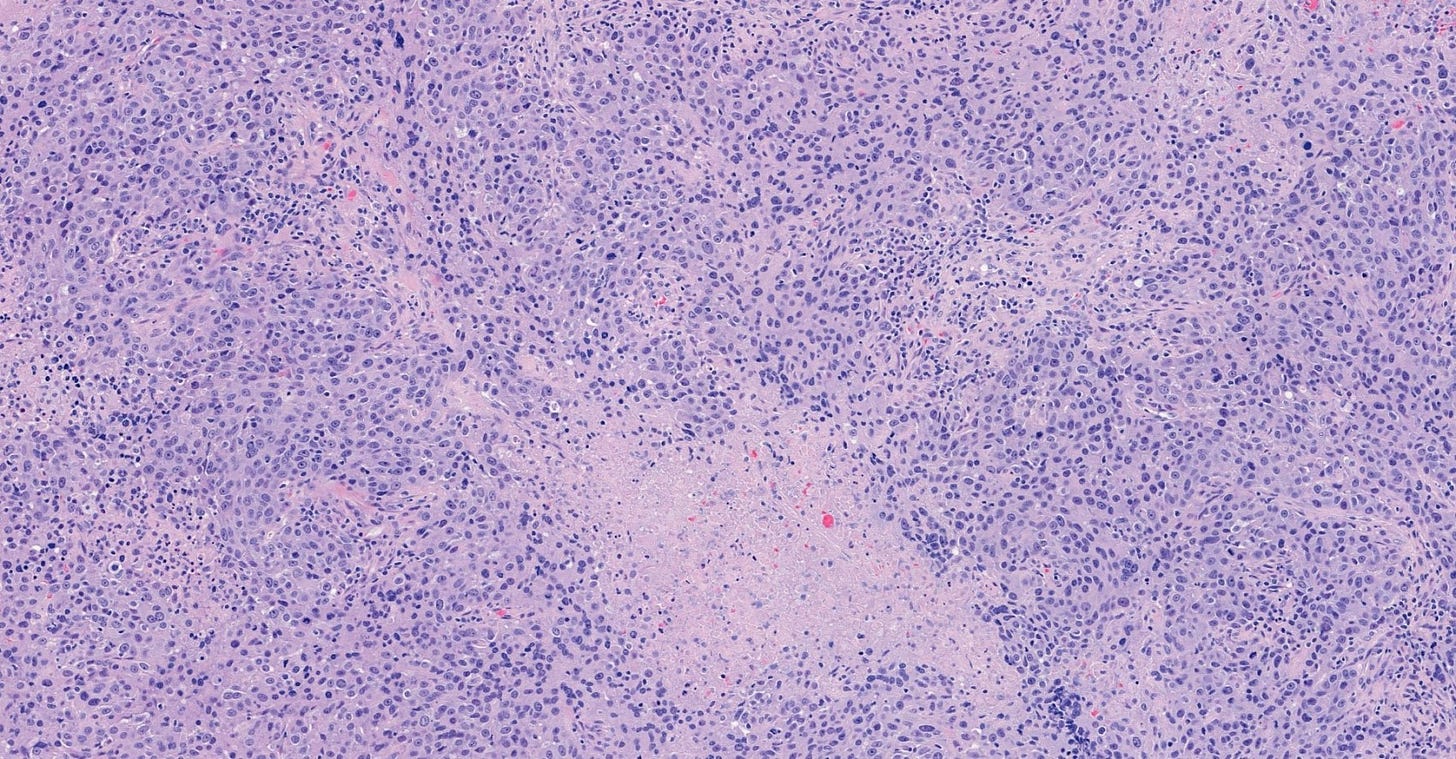

Infiltrating duct carcinoma (IDC) of no special type - microscopic images

The premalignant precursors of invasive duct carcinoma of no special type are DCIS (ductal carcinoma in situ) and classic LCIS (lobular carcinoma in situ). In addition, we speculate that there may be unidentified precursors based on molecular patterns of change without microscopic changes, although this is unproven.